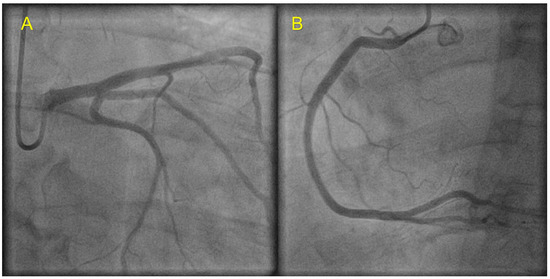

| Echocardiography | Hypokinetic non-dilated cardiomyopathy LVEF = 42% Mild mitral regurgitation IAS aneurysm | Hypokinetic non-dilated cardiomyopathy LVEF = 34% Mild mitral regurgitation IAS aneurysm | Left ventricular concentric hypertrophy LVEF = 54% |

| Cardiac magnetic resonance imaging | Hypokinetic non-dilated cardiomyopathy Left ventricular non-compaction LVEF = 50% | Hypokinetic non-dilated cardiomyopathy Regional sub-epicardial fibrosis LVEF = 41% | Not carried out |

| Coronary angiography | Normal | Normal | Not carried out |